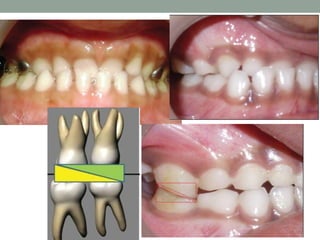

DentalAnterior Cross-bite

• Dental anterior cross-bites are generally the result of an

abnormal eruption of the permanent incisors.

• Dentoalveolar malrelationship

• Normal anterior-posterior skeletal relationship

• #16 Simple anterior cross-bites are generally the result of an abnormal eruption of the permanent incisors. Abnormal eruption of the permanent incisors Dentoalveolar malrelationship Maxillary incisors tipped lingually Mandibular incisors tipped labially Angle Class I relationship Coincident centric occlusion and centric relation May or May not be associated with forced bite. No basal discrepancy Normal anterior-posterior skeletal relationship with a smooth path of mandibular closure. Treated as early as possible in growing patients since it can have activator like functional effect (particularly in forced bite category) leading to basal discrepancy. Most of the cases require only correction of incisal Malrelationship which can be done at any age. It is easy to treat